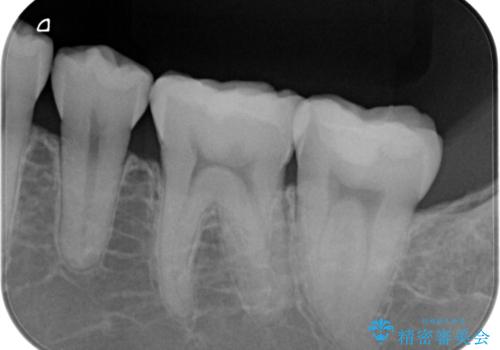

- 左下の銀歯の横から小さい虫歯になっていたため治療しました。

- 15.4万円(emaxインレー 7.7万円x2本)費用は治療当時の料金となります

自費のインレーは、ゴールドかセラミックが選択可能です。

今回は患者様のご希望によりセラミックとなりました。

治療は歯型とり、インレーの装着の2回かかります。